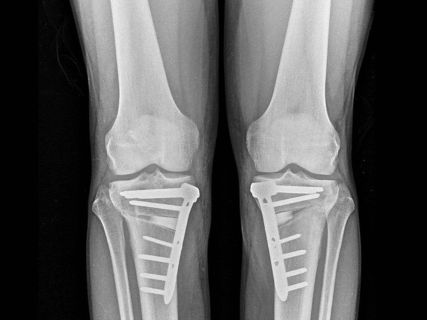

El doctor Juan Arnal, destacado especialista en Cirugía Ortopédica y Traumatología en el Hospital Universitario Gregorio Marañón de Madrid, ha resaltado la eficacia de la osteotomía para “retrasar durante décadas o, incluso, evitar la necesidad de una prótesis” de rodilla en pacientes con predisposiciones genéticas a la degeneración articular.

Esta intervención corrige anomalías en las piernas como el ‘genu varo’, que causa una curvatura externa de las rodillas, y el ‘genu valgo’, que provoca una forma en ‘X’ de las piernas, conservando la articulación natural y combatiendo la progresión de la artrosis sin recurrir a implantes protésicos.

AVANCES TECNOLÓGICOS

La técnica de la osteotomía se lleva a cabo mediante un corte preciso en el hueso (tibia o fémur) para ajustar la carga en la pierna, redistribuyendo el peso sobre la articulación y mitigando el dolor. El doctor Arnal ha destacado la transformación de esta técnica debido a avances como la planificación digital tridimensional y nuevos sistemas de fijación e implantes. “Hoy podemos planificar en el ordenador la corrección exacta y, si lo deseamos, imprimir en 3D guías quirúrgicas personalizadas. Además, los nuevos sistemas de fijación permiten que el paciente empiece a apoyar la pierna a las 24 horas”, explicó.